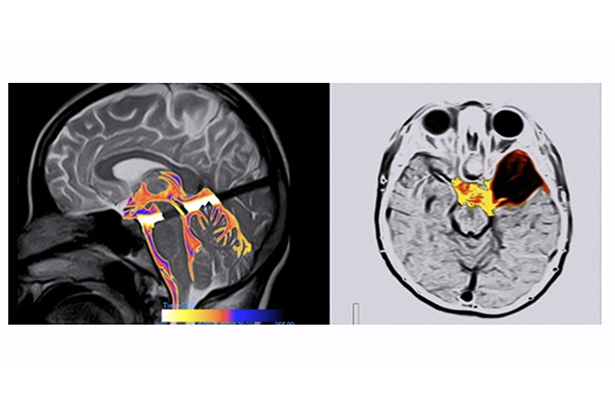

4D流體標記技術利用腦脊液的流動特性,采用選擇性的IR脈沖,對腦脊液進行動態電影成像。對于蛛網膜下腔出血后交通性腦積水、多囊性外傷后腦積水、脊髓空洞癥、中腦導水管狹窄等疾病的成因、早期診斷、預后評價等有研究價值。